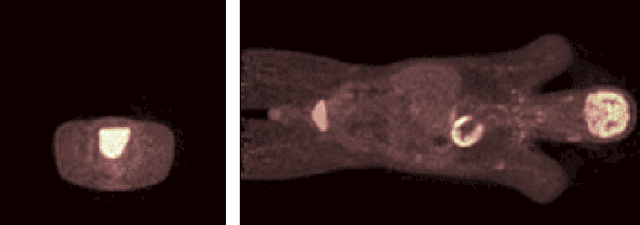

Abstract:Images from positron emission tomography (PET) provide metabolic information about the human body. They present, however, a spatial resolution that is limited by physical and instrumental factors often modeled by a blurring function. Since this function is typically unknown, blind deconvolution (BD) techniques are needed in order to produce a useful restored PET image. In this work, we propose a general BD technique that restores a low resolution blurry image using information from data acquired with a high resolution modality (e.g., CT-based delineation of regions with uniform activity in PET images). The proposed BD method is validated on synthetic and actual phantoms.

Abstract:Improving the quality of positron emission tomography (PET) images, affected by low resolution and high level of noise, is a challenging task in nuclear medicine and radiotherapy. This work proposes a restoration method, achieved after tomographic reconstruction of the images and targeting clinical situations where raw data are often not accessible. Based on inverse problem methods, our contribution introduces the recently developed total generalized variation (TGV) norm to regularize PET image deconvolution. Moreover, we stabilize this procedure with additional image constraints such as positivity and photometry invariance. A criterion for updating and adjusting automatically the regularization parameter in case of Poisson noise is also presented. Experiments are conducted on both synthetic data and real patient images.